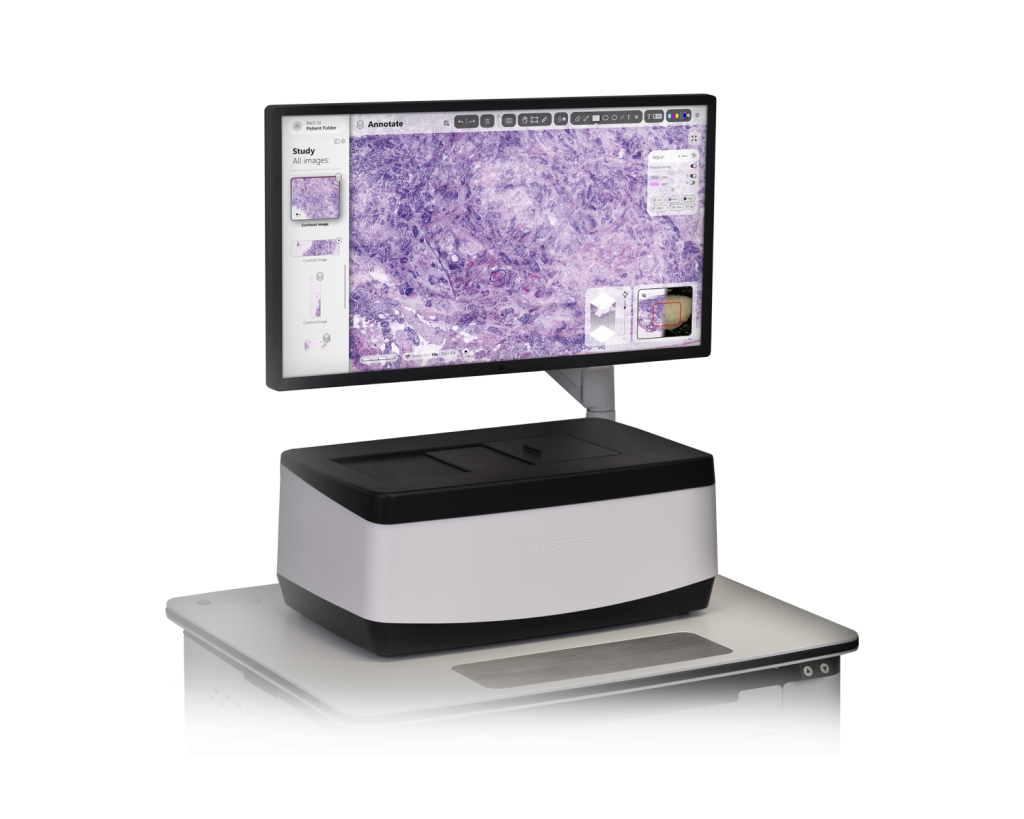

The glass slide is subsequently inserted into the VivaScope 2500.

Step 4: Confocal Imaging

The VivaScope 2500 rapidly scans the excised tissue and reveals the cellular

morphology.